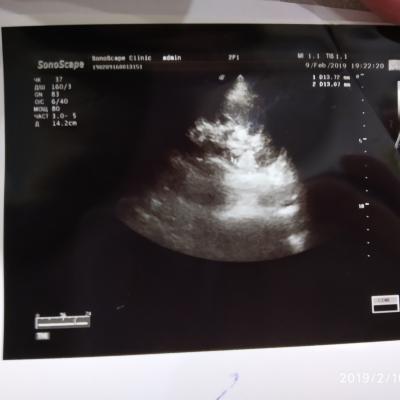

Здравствуйте. Кардиолог направил на УЗИ почек и надпочечников (иногда повышение АД и постоянно высокий пульс). У нас в городе нет врача уролога. Поеду в областной центр как только смогу записаться на приём врача. Помогите расшифровать результаты УЗИ. Я почитала что можно носить бандаж, чтобы удерживать почку на месте. Можно ли мне в моей ситуации носить бандаж? И про левую почку врач УЗИ сказала про какие-то сосуды, сказала просто повторно пройти обследование через полгода, а в результате читаю липома? Спасибо.

Здравствуйте! Надо сделать МСКТ( мультиспиральная компьютераня томография) почек, мочеточников. А потом наблюдать уже можно - УЗИ. По поводу нефроптоза - бандаж носить можно. И укреплять мышцы передней брюшной стенки. Удачи!